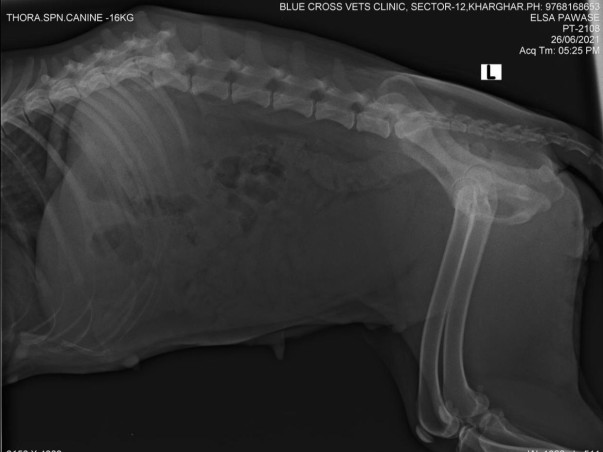

•Elsa: She is a victim of a road accident. An irresponsible rescuer instead of doing her treatment, dumped her at a sterilization centre. Now her condition is very critical. She has many maggot wounds on her hip, bedsores, kidney malfunction, severe UTI and a broken spine that lead to paralysis.

Currently, she is admitted to the hospital & is fighting for her life.

Cost breakdown:

1st vet visit- 3788/-

Hospital Admission Charges- 5000/-

Foster charges after discharge from hospital- 18k for stay (300 per day)

Future vet visits/transportation/meds/blood tests which shall happen on weekly basis/ hydrotherapy/ physiotherapy/Acupuncturist - At least 9k

Total funds needed for ELSA - 35k